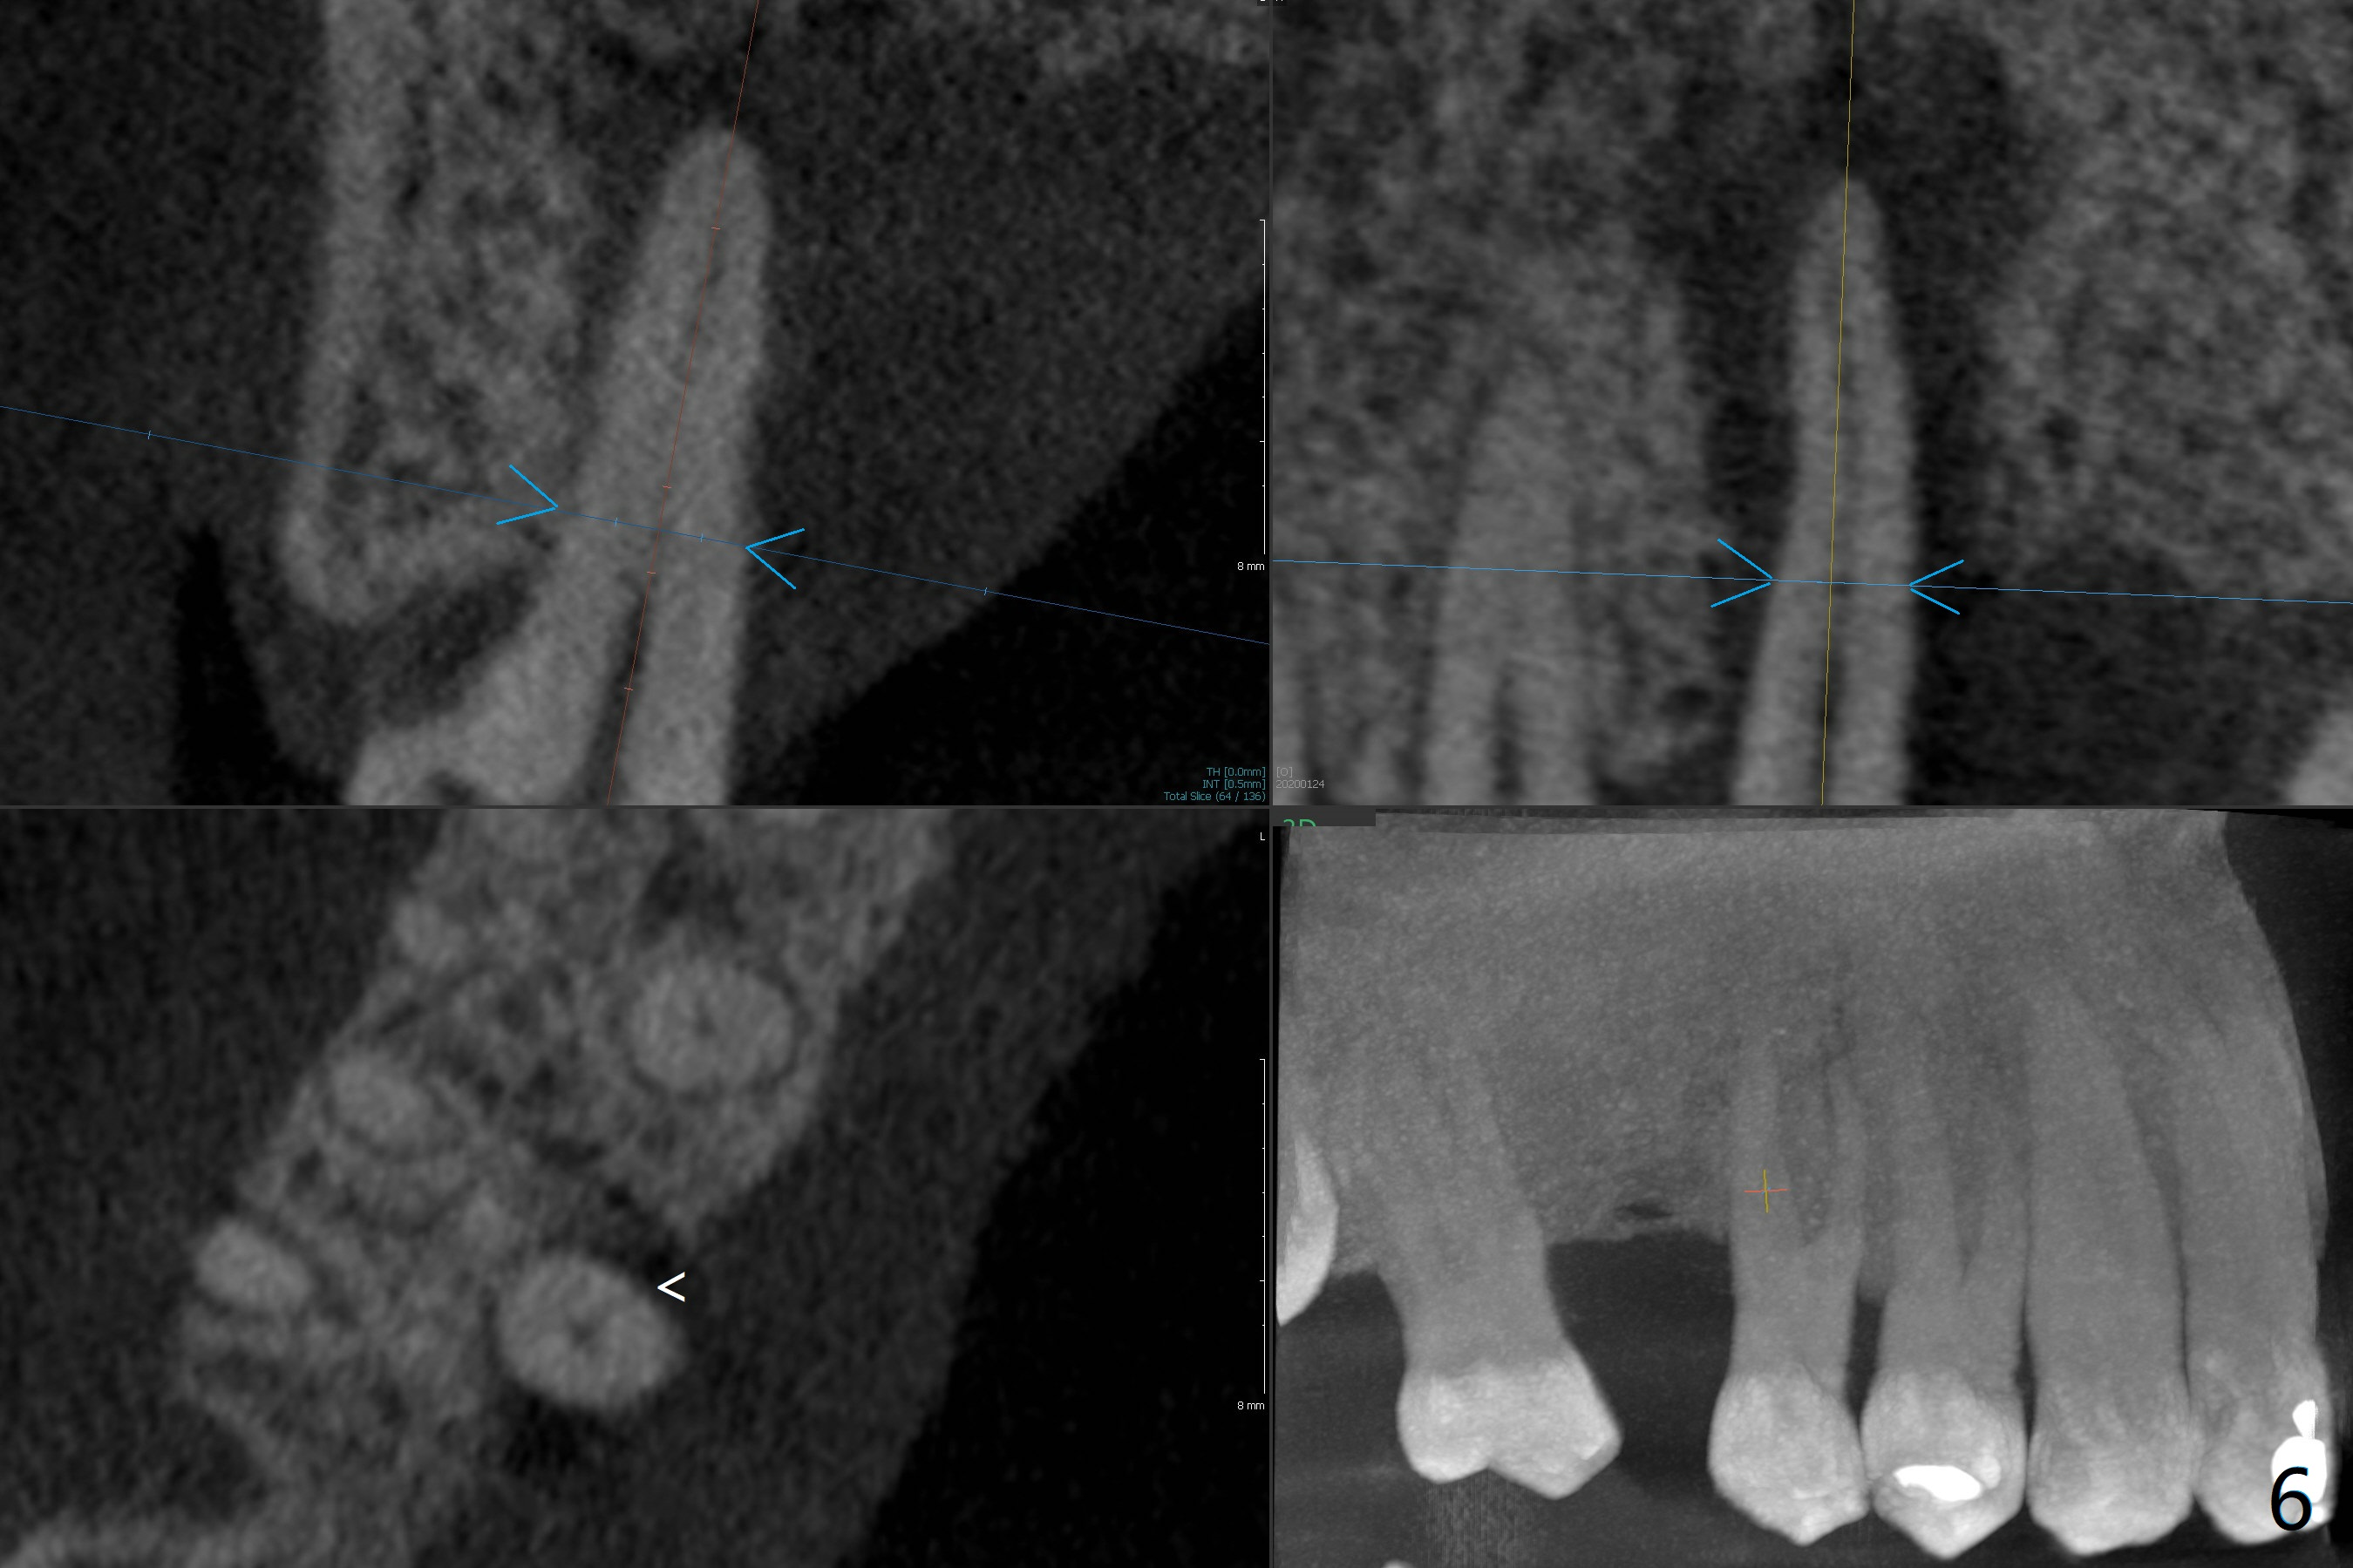

A 52-year-old man (smoker 1 ppd) has toothache in UR. The tooth #4 has severe Class V defect (Fig.1 *), periapical radio-lucency (PARL, arrow-heads) around the buccal roots and mild percu-ssion. PARL is more severe around the palatal root (Fig.2 P). Since it seems difficult to do socket preser-vation, can we do RCT to regrow bone before implant? CT coronal section shows the palatal defect of the palatal root (Fig.3,4), while sagittal one shows J defect of the palatal root, associated with root fracture (Fig.5). In fact the palatal root has transverse fracture at crestal level (Fig.6-8). The tooth #4 will be extracted for immediate implant (Fig.9,10); a 4 mm implant will be placed in the narrow space of #3 at the same time (Fig.11). The patient had symptoms consistent with aortic aneurysm. Since then smoke has been quit.